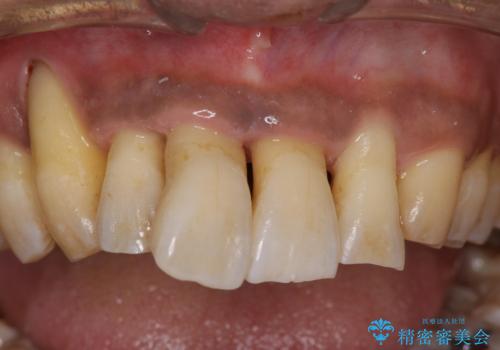

- 歯並びが気になり矯正をしたいと来院された。歯周病の検査、レントゲンをとり重度の歯周病であることがわかりました。

まずは、歯周病の初期治療から行っていくことを説明。

黒々とした厚みのある歯石が歯の表面に沢山付いていました。

痛みもなかったため(冷たいものでしみる知覚過敏症状はある)びっくりされていた印象です。